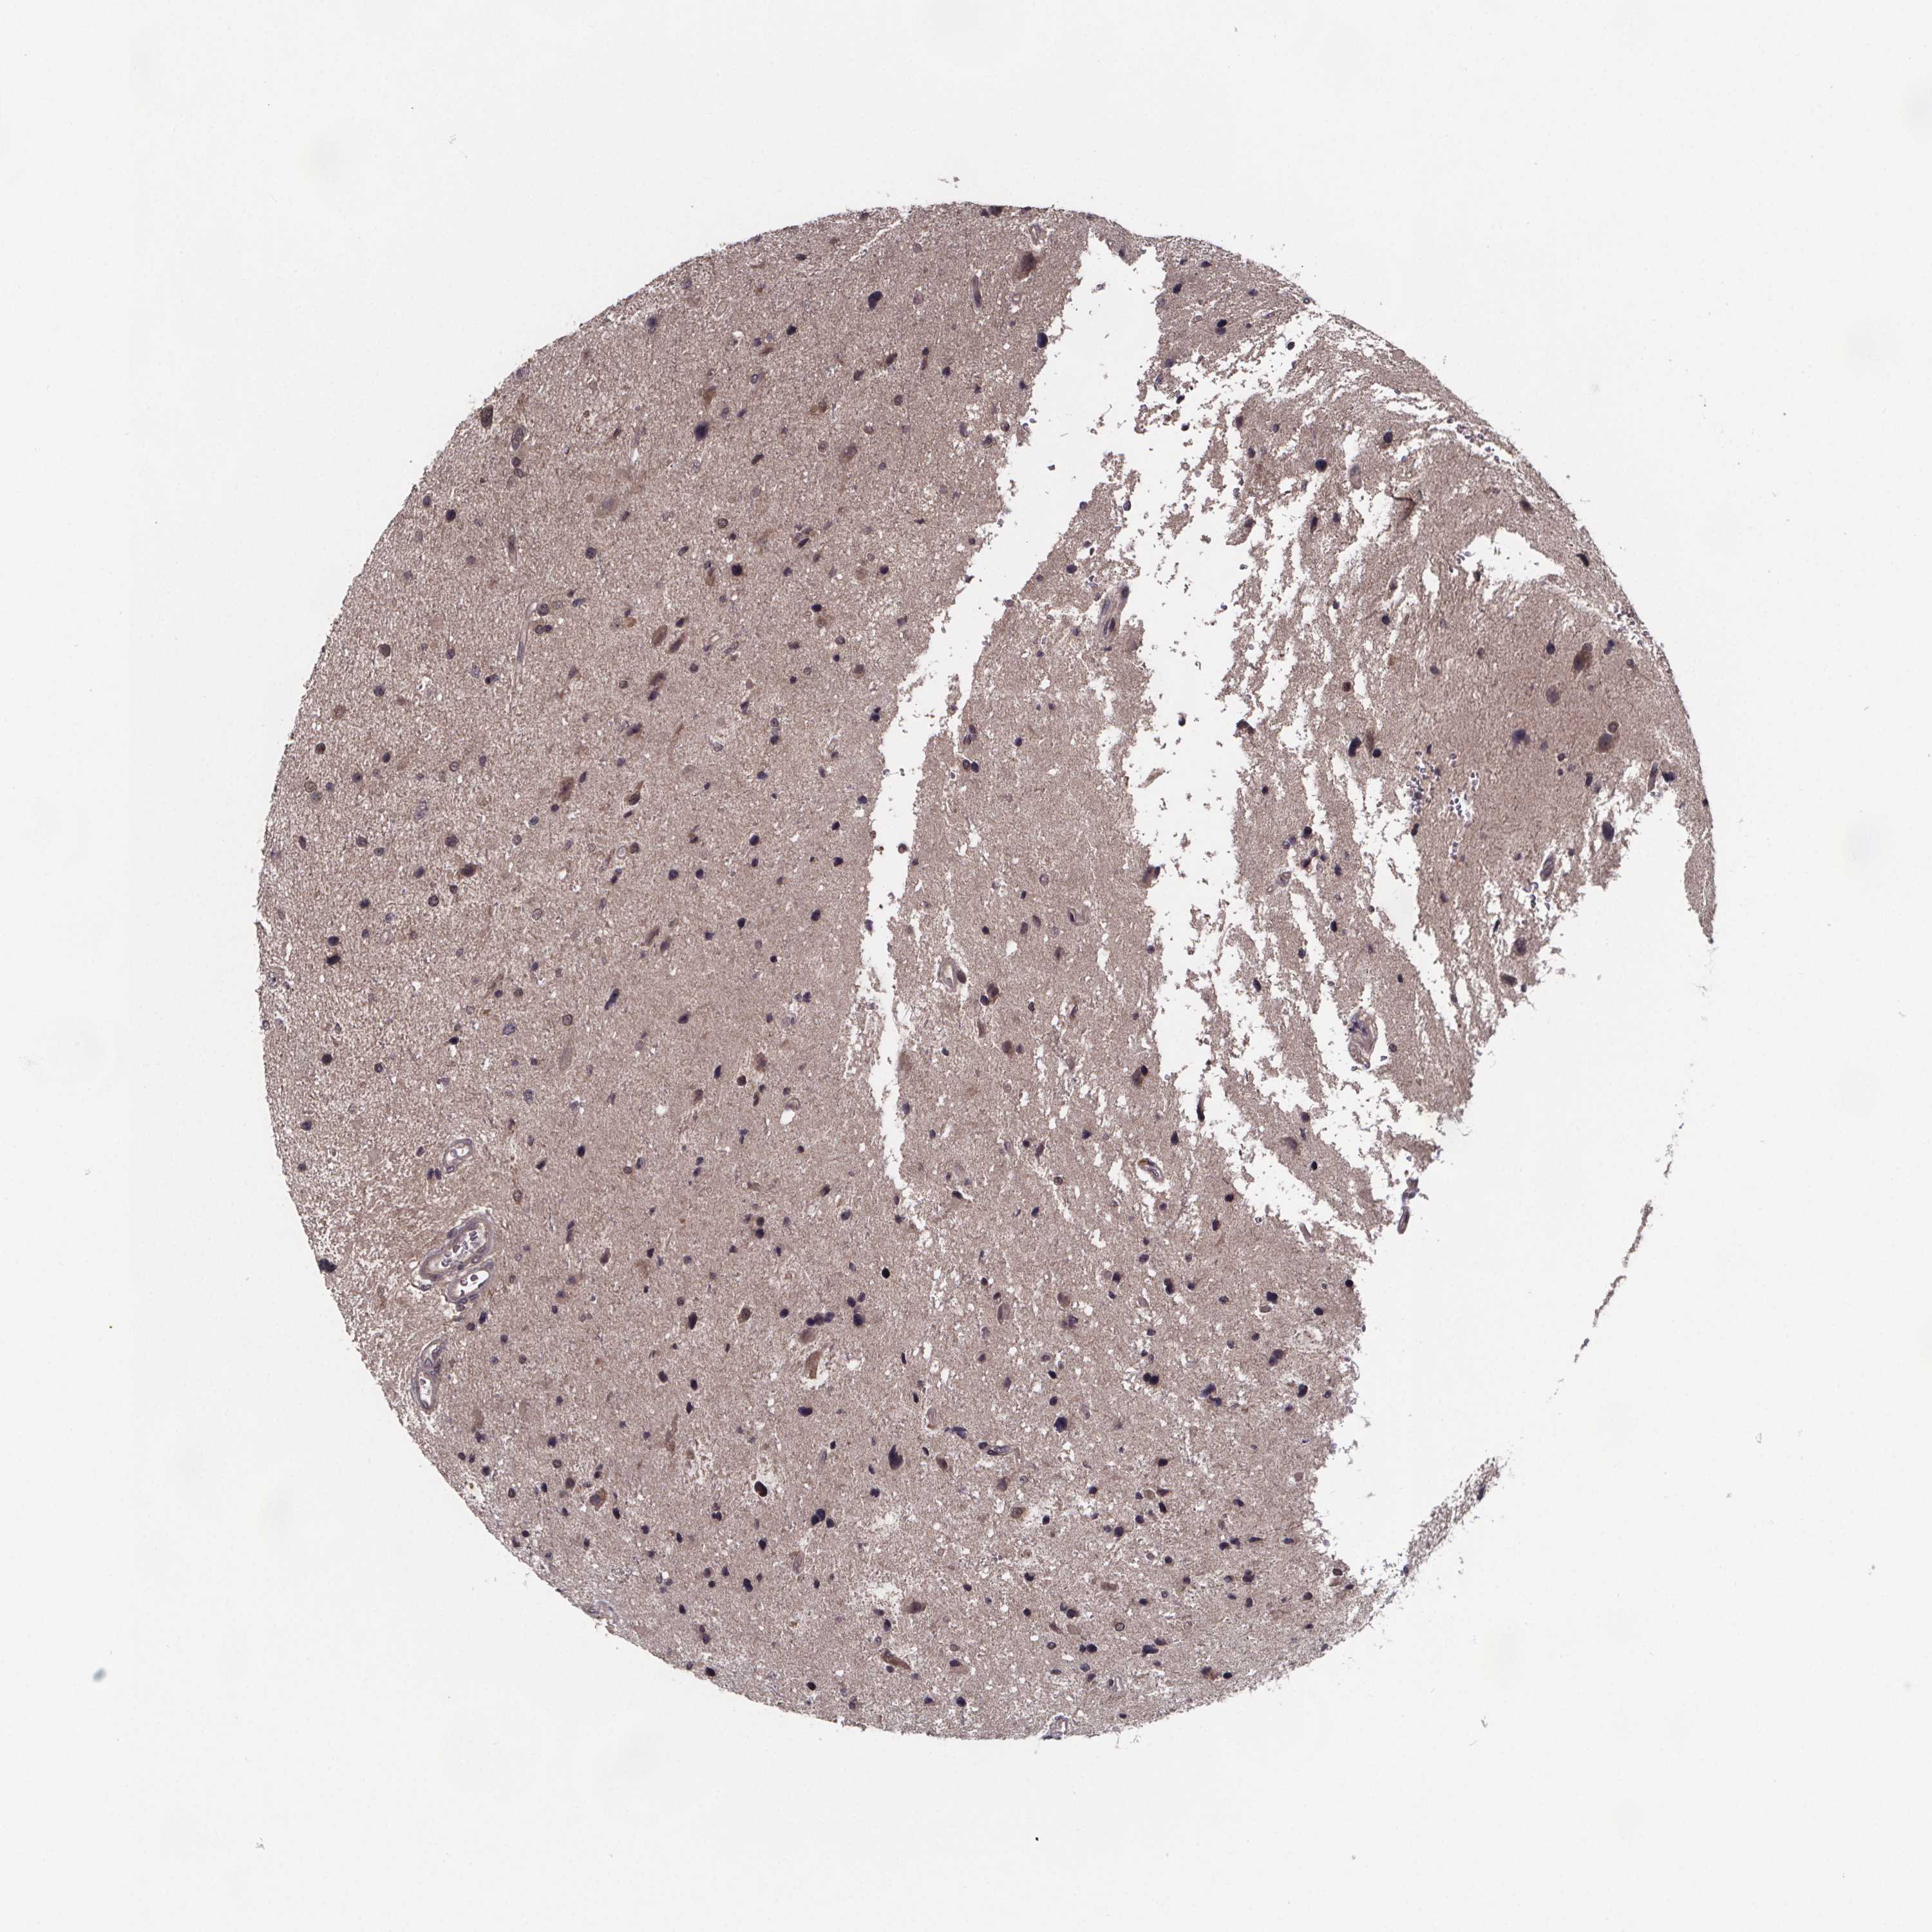

GLIOMA - Protein expressioni

A mouse-over function shows sample information and annotation data. Click on an image to view it in a full screen mode. Samples can be filtered based on level of antibody staining by selecting one or several of the following categories: high, medium, low and not detected. The assay and annotation is described here.

Note that samples used for immunohistochemistry by the Human Protein Atlas do not correspond to samples in the TCGA dataset.

Antibody stainingi

Antibody staining in the annotated cell types in the current human tissue is reported as not detected, low, medium, or high, based on conventional immunohistochemistry profiling in selected tissues. This score is based on the combination of the staining intensity and fraction of stained cells.

Each image is clickable and will lead to virtual microscopy that enables deeper exploration of all samples and also displays staining intensity scores, fraction scores and subcellular localization as well as patient and tissue information for each sample.

Antibody HPA065831

Staining

High

Medium

Low

Not detected

Intensity

Strong

Moderate

Weak

Negative

Quantity

>75%

75%-25%

<25%

None

Location

Nuclear

Cytoplasmic/membranous

Cytoplasmic/membranous,nuclear

Glioma, malignant, Low grade

Glioma, malignant, High grade